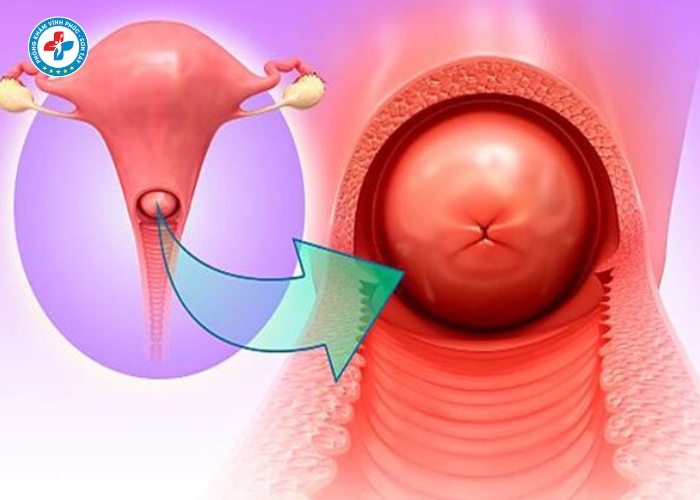

Lộ tuyến cổ tử cung là gì?

Lộ tuyến cổ tử cung là tình trạng các tế bào tuyến bên trong cổ tử cung phát triển và xâm lấn ra mặt ngoài cổ tử cung. Những tế bào này tiết dịch nhiều hơn bình thường, tạo môi trường thuận lợi cho vi khuẩn phát triển.